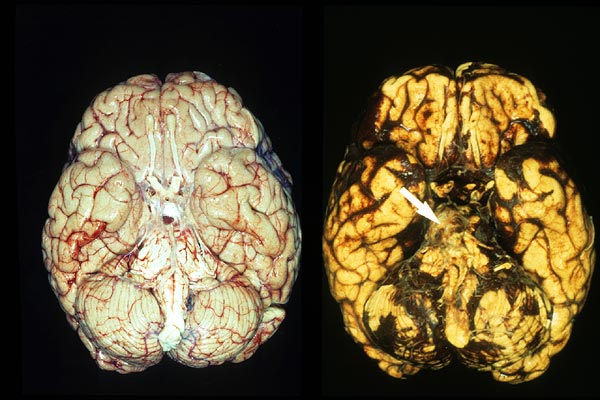

Subarachnoidale Blutungen

Schweres Schädeltrauma